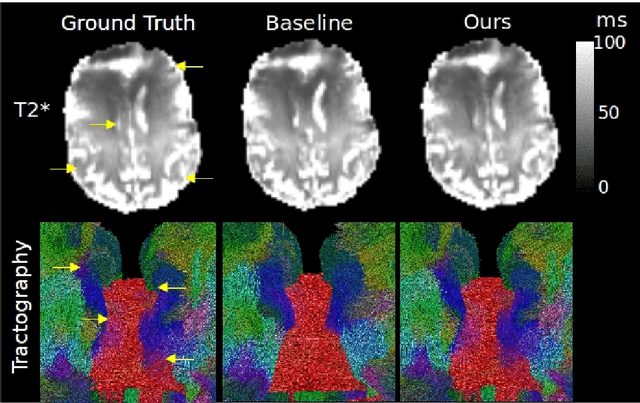

We present PROSUB: PROgressive SUBsampling, a deep learning based, automated methodology that subsamples an oversampled data set (e.g. multi-channeled 3D images) with minimal loss of information. We build upon a recent dual-network approach that won the MICCAI MUlti-DIffusion (MUDI) quantitative MRI measurement sampling-reconstruction challenge, but suffers from deep learning training instability, by subsampling with a hard decision boundary. PROSUB uses the paradigm of recursive feature elimination (RFE) and progressively subsamples measurements during deep learning training, improving optimization stability. PROSUB also integrates a neural architecture search (NAS) paradigm, allowing the network architecture hyperparameters to respond to the subsampling process. We show PROSUB outperforms the winner of the MUDI MICCAI challenge, producing large improvements >18% MSE on the MUDI challenge sub-tasks and qualitative improvements on downstream processes useful for clinical applications. We also show the benefits of incorporating NAS and analyze the effect of PROSUB's components. As our method generalizes to other problems beyond MRI measurement selection-reconstruction, our code is https://github.com/sbb-gh/PROSUB